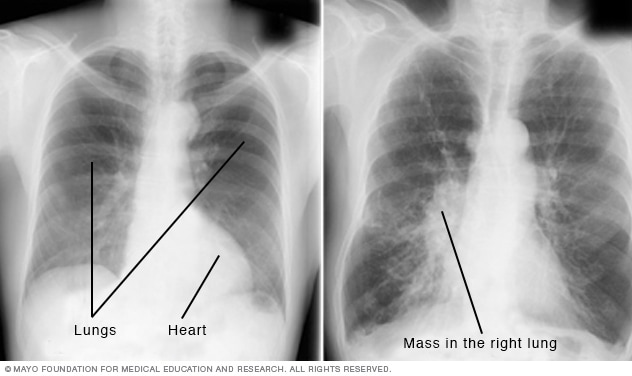

تصوير الصدر بالأشعة السينية Mayo Clinic مايو كلينك

الأشعة السينية هي اختبار تصوير يساعد على سرعة التشخيص Mayo Clinic مايو كلينك

الأشعة السينية هي اختبار تصوير يساعد على سرعة التشخيص Mayo Clinic مايو كلينك

اطمن على نفسك الأشعة على الصدر تساعد فى تشخيص أمراض القلب اليوم السابع

Pneumonia Radiology Reference Article Radiopaedia Org